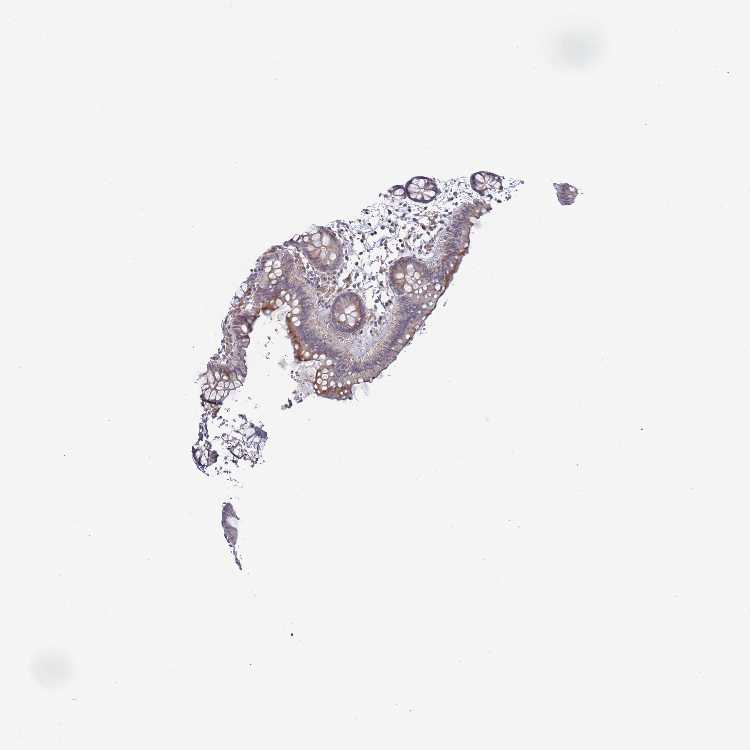

COLON - Antibody stainingi

Antibody staining in the annotated cell types in the current human tissue is reported as not detected, low, medium, or high, based on conventional immunohistochemistry profiling in selected tissues. This score is based on the combination of the staining intensity and fraction of stained cells.

Each image is clickable and will lead to virtual microscopy that enables deeper exploration of all samples and also displays staining intensity scores, fraction scores and subcellular localization as well as patient and tissue information for each sample.

Antibody HPA046800

Endothelial cells Not detected

Glandular cells Medium

Peripheral nerve/ganglion Not detected